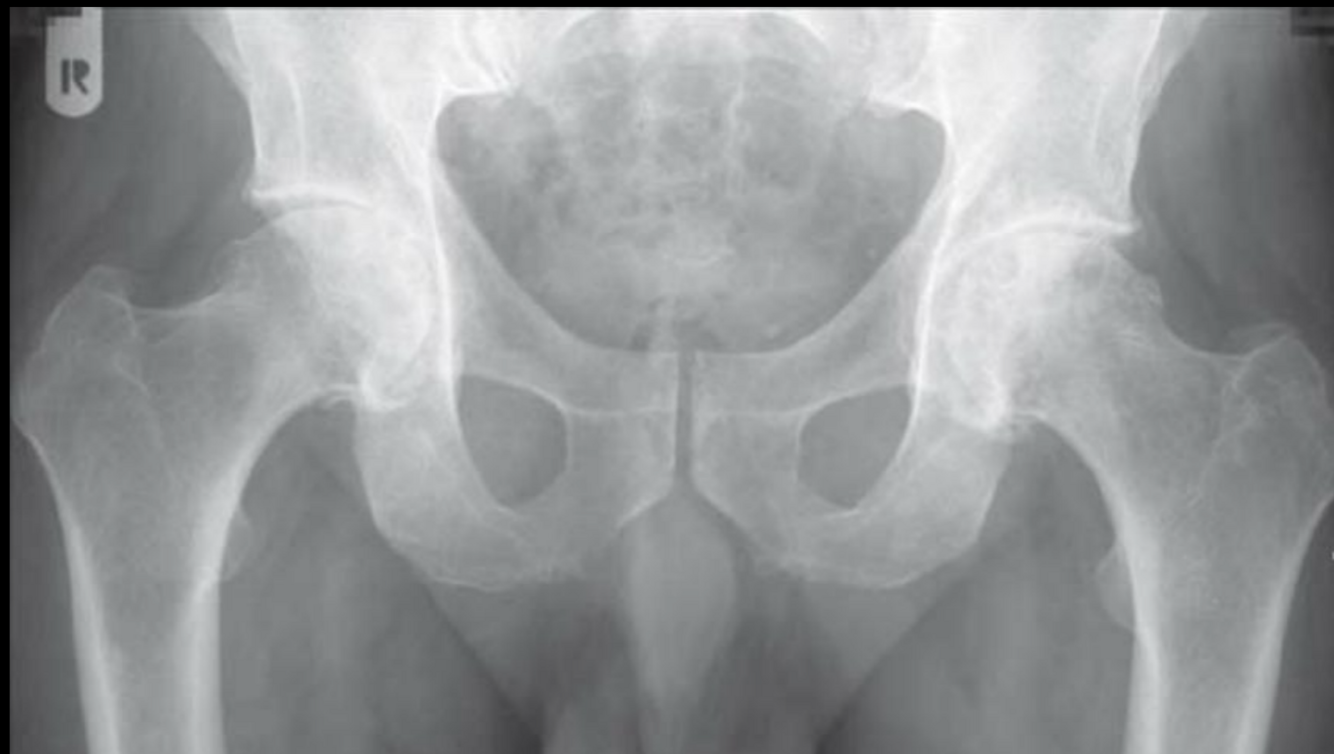

Datos de coxartrosis Rx

A

Disminución del espacio articular

Osteofitos

Esclerosis subcondral

Quistes subcontrates (geodas)

Deformidad

Coxartrosis